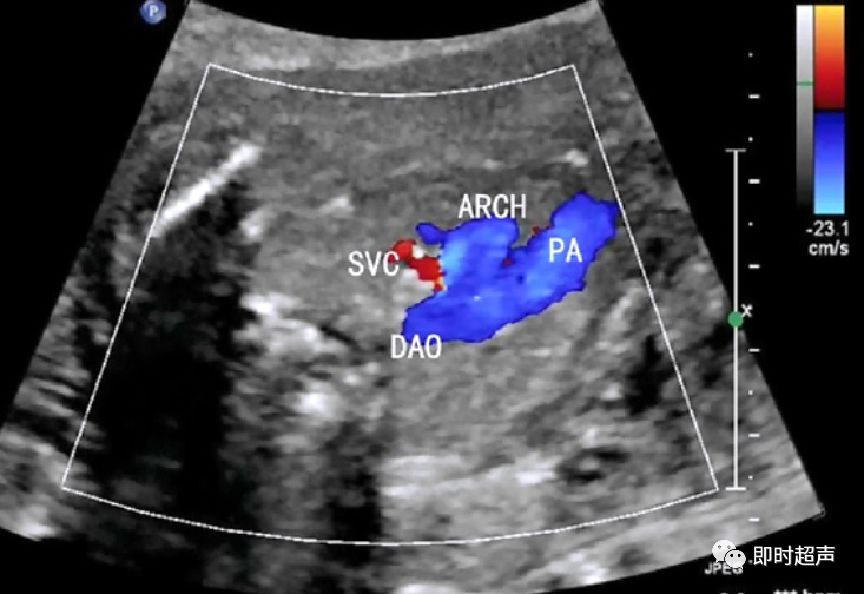

- 肺动脉和主动脉弓血流都流向脊柱,呈后向血流

- 肺动脉经动脉导管与主动脉弓共同汇入降主动脉

五、血流方向的异常

主动脉弓或肺动脉血流方向相反是导管依赖型心脏畸形的典型表现